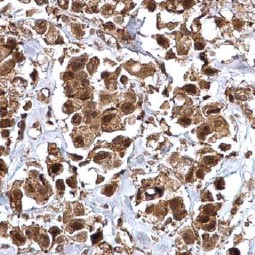

![IL3 Receptor alpha antibody [N2C2], Internal (GTX101563) IL3 Receptor alpha antibody [N2C2], Internal (GTX101563)](/upload/media/research/Cancer/Cancer_Stem_Cells/GTX101563.jpg)